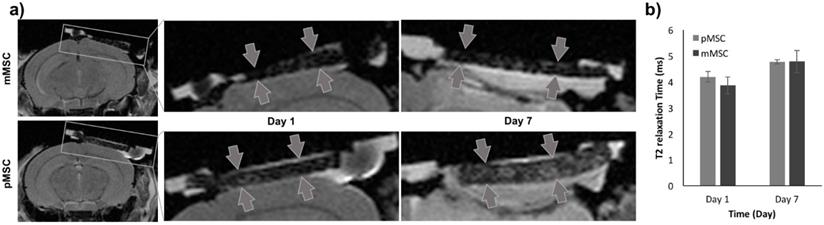

To evaluate the Feru-AFC NPs in vivo, we delivered them into mMSCs (matched) and pMSCs (mismatched) before transplanting them into female C57BL/6J mice with calvarial defects (n = 6). We used MRI to localize the Feru-AFC-treated mMSCs and pMSCs seeded in the scaffold (Figure 4a). In vivo MRI of the Feru-AFC NP-treated mMSC and pMSC transplants did not reveal any significant differences in T2 relaxation time at days 1 and 7 after implantation (p = 0.43 and p = 0.98, respectively) (Figure 4b).

MRI to localize implanted Feru-AFC-labeled mMSCs and pMSCs in mouse calvarial defects. (a) Representative images from MRI of mouse (matched) and pig (mismatched) MSCs transplants (arrows) in calvarial defects, 1 and 7 days after implantation. (b) Corresponding quantitative analysis from MRI of matched and mismatched MSCs in calvarial defects (p > 0.05 for pMSCs versus mMSCs on days 1 and 7).

While in vivo MRI enabled localization of cell transplants in skull defects on day 1, we did not observe significant signal differences between the matched (mMSCs) and mismatched (pMSCs) implants at day 7 post transplantation (Figure 4). In accordance with other studies,53 we showed that the iron oxide signal on MR images could persist after the death of labeled cells; this may be due to slow iron metabolism, macrophage/microglial behaviors, and/or our short follow-up period. The carboxymethyldextran is cleaved by dextranase and excreted by the kidneys. The iron core is incorporated into the bodies iron store and slowly metabolized over time. The T2-signal is not linearly related to iron concentration. The initially high local iron concentration at the transplant site likely decreased over time, but not enough to change the T2-value within the first 7 days. There is a possibility that the released irons are engulfed in the local macrophages and get degraded slowly.